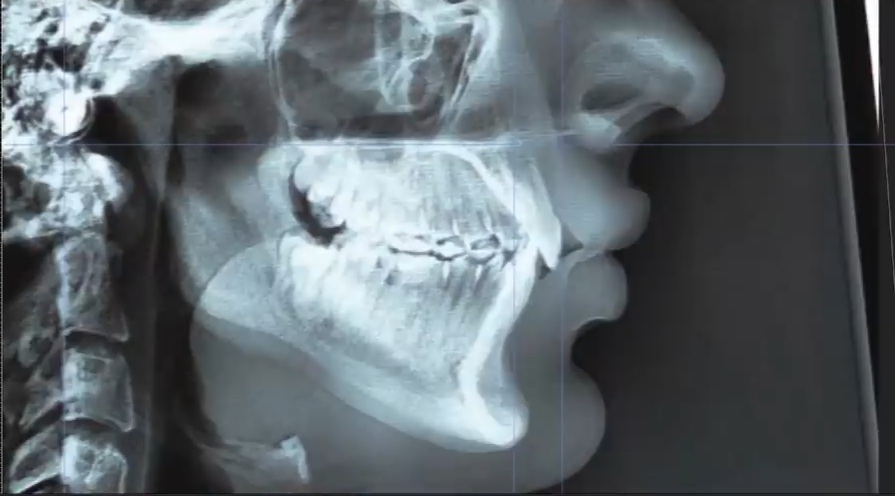

These are the forces acting upon the maxilla when the premolars are in contact:

Upwards force on the front only. There will be a CCW rotation and this is definitely what you want. It's clear as day. However, since it is not right on the front edge the change will take slightly slower than if you were to keep the molars in contact.